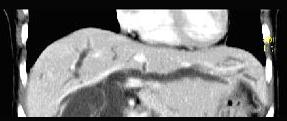

问题 患者,男,51岁,右上腹隐痛两月余,CT扫描如图,最可能的诊断是()

选项 A.胆囊癌伴肝门胰头周围转移 B.胆囊息肉 C.胆囊黄色肉芽肿 D.慢性胰腺炎并胆囊息肉 E.胆囊腺瘤及慢性胰腺炎

答案 A